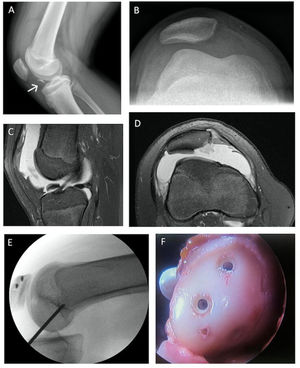

Centros de osificación y lesión fisiaria de tibia proximal. (A) Esquema de los centros de osificación de la tibia proximal (visión lateral): Centro de osificación primario (1) y secundario (2). (B y C) Radiografía anteroposterior (A) y lateral (B) de avulsión de la tuberosidad anterior de la tibia. (D y E) Imágenes de tomografía computada de rodilla, confirmando la fractura avulsiva Tipo Ogden III, con un rasgo coronal que compromete el centro de osificación secundario y primario de la tibia proximal. (F y E) Radiografía anteroposterior y lateral tras la reducción abierta y fijación interna de la fractura avulsiva con dos tornillos canulados 4.0mm paralelos a la fisis. (Ref. 5).

Las radiografías AP y lateral proporcionan información inicial sobre el tipo y extensión de la fractura y son parte del estudio inicial. La tomografía axial computada (TAC) no es mandatoria, pero permite caracterizar mejor el grado de conminución o la extensión articular de la fractura y ayuda a planificar el tratamiento quirúrgico. La resonancia magnética (RM) permite descartar lesiones asociadas como roturas meniscales o ligamentosas, recomendándose en el estudio de aquellas avulsiones con extensión articular y desplazamientos significativos5.

La clasificación más comúnmente utilizada para las fracturas de la TAT es la de Ogden modificada. En términos generales esta clasificación se divide en 5 tipos dependiendo de la orientación y extensión ya sea de uno o ambos centros de osificación de la tibia proximal. Siendo las tipo I puramente avulsiones de la tuberosidad anterior de la tibia, las tipo II avulsiones que se extienden entre ambas fisis sin comprometer la articulación, las tipo III avulsiones con compromiso articular, tipo IV avulsiones que se extienden a través de toda la tibia proximal en sentido anteroposterior y las tipo V una combinación entre tipo III y IV. A su vez la clasificación considera la ausencia de desplazamiento como un subtipo “a” o la presencia de este como subtipo “b” 8,10.

El 88% de estas lesiones va a requerir un tratamiento quirúrgico, que puede consistir en una reducción cerrada y fijación percutánea o una reducción abierta y fijación con tornillos11 (Figura 1). La fijación de estas fracturas avulsivas debe realizarse con tornillos o agujas paralelas a la fisis (cartílagos de crecimiento) para evitar daño secundario o bloquear su potencial de crecimiento. La asistencia artroscópica puede ser una herramienta útil para lograr una adecuada reducción articular, minimizar el abordaje y tratar lesiones asociadas. Sin embargo, debemos tener en cuenta el riesgo de un síndrome compartimental, y evitarlo mediante artroscopias secas o de baja presión y corta duración11. La rehabilitación postoperatoria consiste en 6 semanas de inmovilizador en extensión, marcha con dos bastones y carga parcial. El reintegro deportivo depende de la magnitud de la lesión y oscila entre los 4-6 meses.